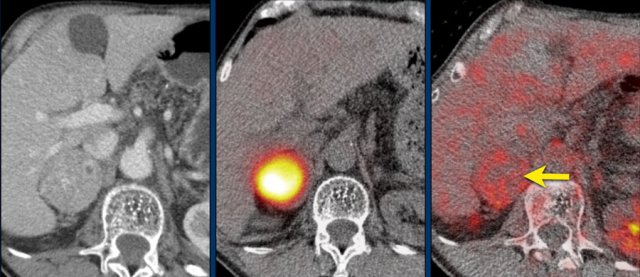

Axial venous phase CT in mediastinal and bone window setting Axial venous phase CT in mediastinal and bone window setting

Images depict mediastinal and bone window setting of a patient with a bulky heterogeneously enhancing right adrenal tumor.

This was proven to be an adrenocortical carcinoma.

There is a faint, ill-defined liver lesion in segment 6 and there are non-specific sclerotic changes in the body of T12.

Continue with the PET-image...

PET-CT performed for complete staging shows intense uptake in the adrenal tumor, indicative of its malignant nature.

There is also intense uptake in two liver metastases and in a bone metastasis in T12.

Approximately 20-40% of patients with an adrenocortical carcinoma present with metastases at diagnosis.

Whole-body FDG PET-CT can distinguish benign from malignant lesions with high sensitivity (100%), but with lower specificity (87- 97%).